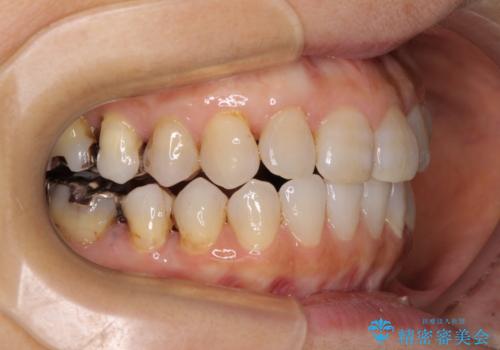

前歯の突出感と上下の隙間 インビザラインによる矯正治療

- 前歯の上下スペースと前歯の隙間を気にして来院された患者様です。

インビザラインにより上下の前歯の隙間を閉じながら、IPRを用いて口元の突出感を合わせて改善していくこととしました。

上下の隙間に舌が入り込むことが、すきっ歯やオープンバイトの原因であったため、舌の筋肉のトレーニングも並行して行い、後戻りの抑制を図りました。